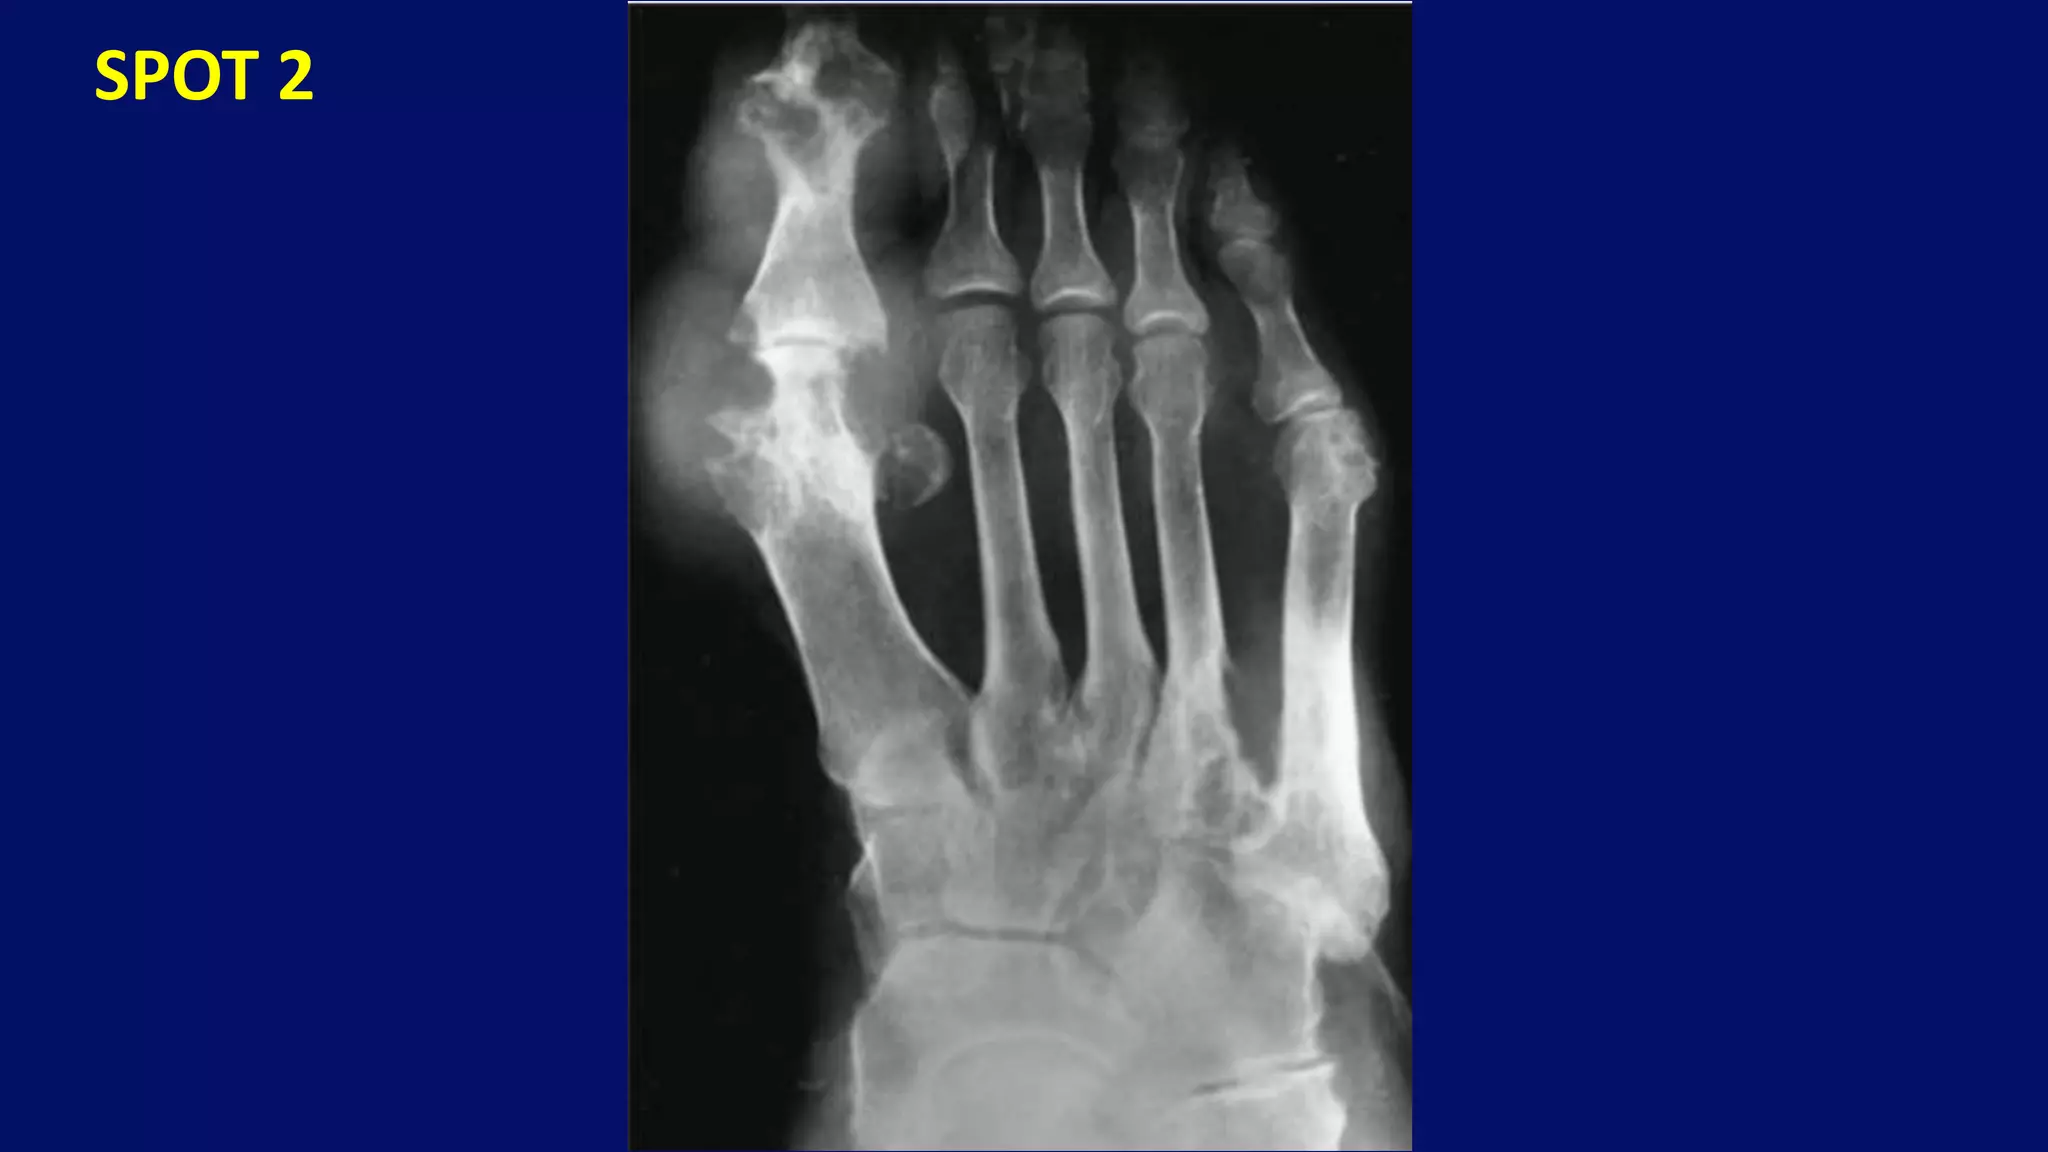

SPOT 2

• #35 Dorsoplantar radiograph of the great and second toes of the feet of a 33-year-old man shows osteoarthritis of the first metatarsophalangeal joints, which are known as hallux rigidus (hallux limitus). Note the narrowing of the joint space, subchondral sclerosis, and marginal osteophytes. Degenerative arthritis and stiffness due to bone spurs that affects the MTP joint at the base of the hallux (big toe) is called hallux rigidus or stiff big toe.

• #52 Diabetes, Foot. Note that the distal metatarsals are tapered, producing a licked candy stick configuration.